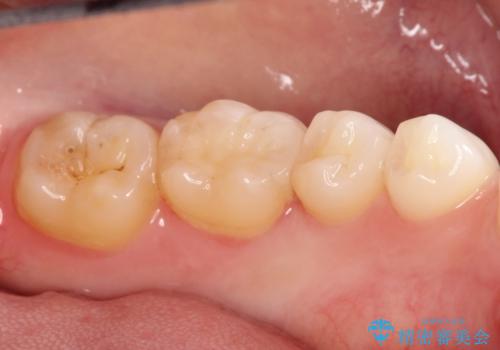

- 金属の詰め物がはずれてしまったので、精度の良いセラミックをいれたいのとのこと来院されました。

セラミックインレーにて治療することとなりました。

拡大鏡を使用して精度の高いインレーを装着しました。